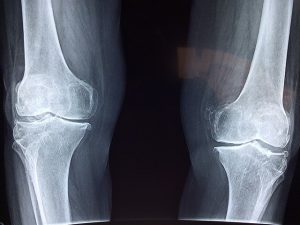

אחד המושגים שרבים רוצים וצריכים להכיר הוא המושג 'נפגע עבודה', בעוד שבמקום בו אנו מרוויחים את עמל יומנו, אנחנו יכולים להיפצע ולהיפגע, בין אם בתאונה בתוך המרחב או בשל מחלת עבודה, ובין אם בשל פגיעה שקרתה בדרך לעבודה. כמו במקרים של תאונות דרכים, נפילה, פציעה ועוד. בעקבות אותה פציעה או מחלה, מפצה הביטוח הלאומי את […]